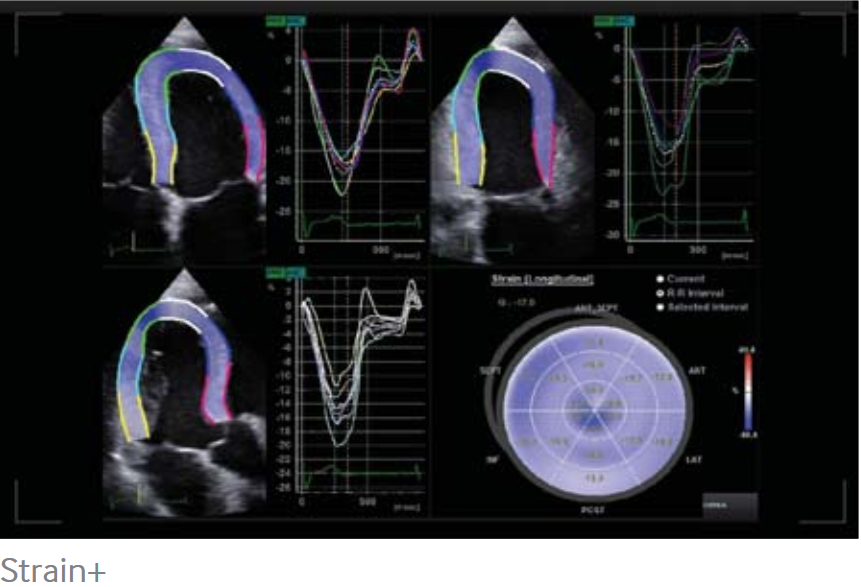

Strain+

El Strain+ es una herramienta cuantitativa para el movimiento de la pared global y segmentaria del ventrículo izquierdo (VI). En el Strain +, se muestran tres panoramas LV estándar y una diana en una pantalla cuádruple para una evaluación fácil y rápida de la función del ventrículo izquierdo.